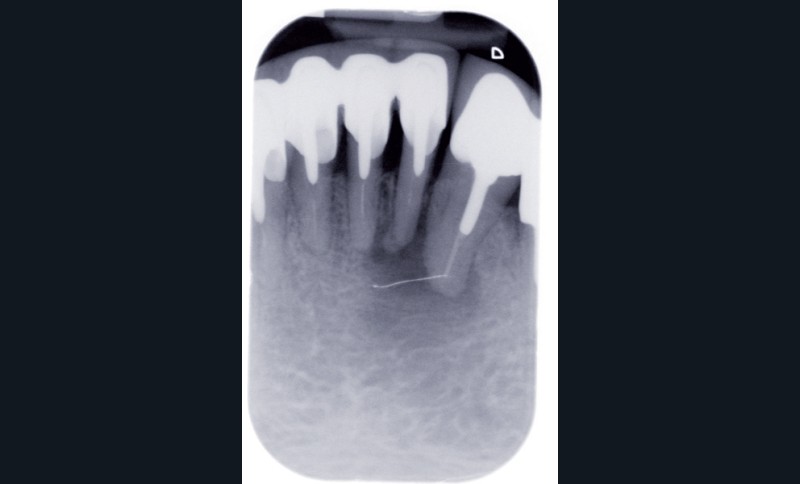

Le contrôle radiologique rétro-alvéolaire montre, quant à lui, une parfaite préservation de l’ostéointégration à 6 ans(fig. 3a et b).